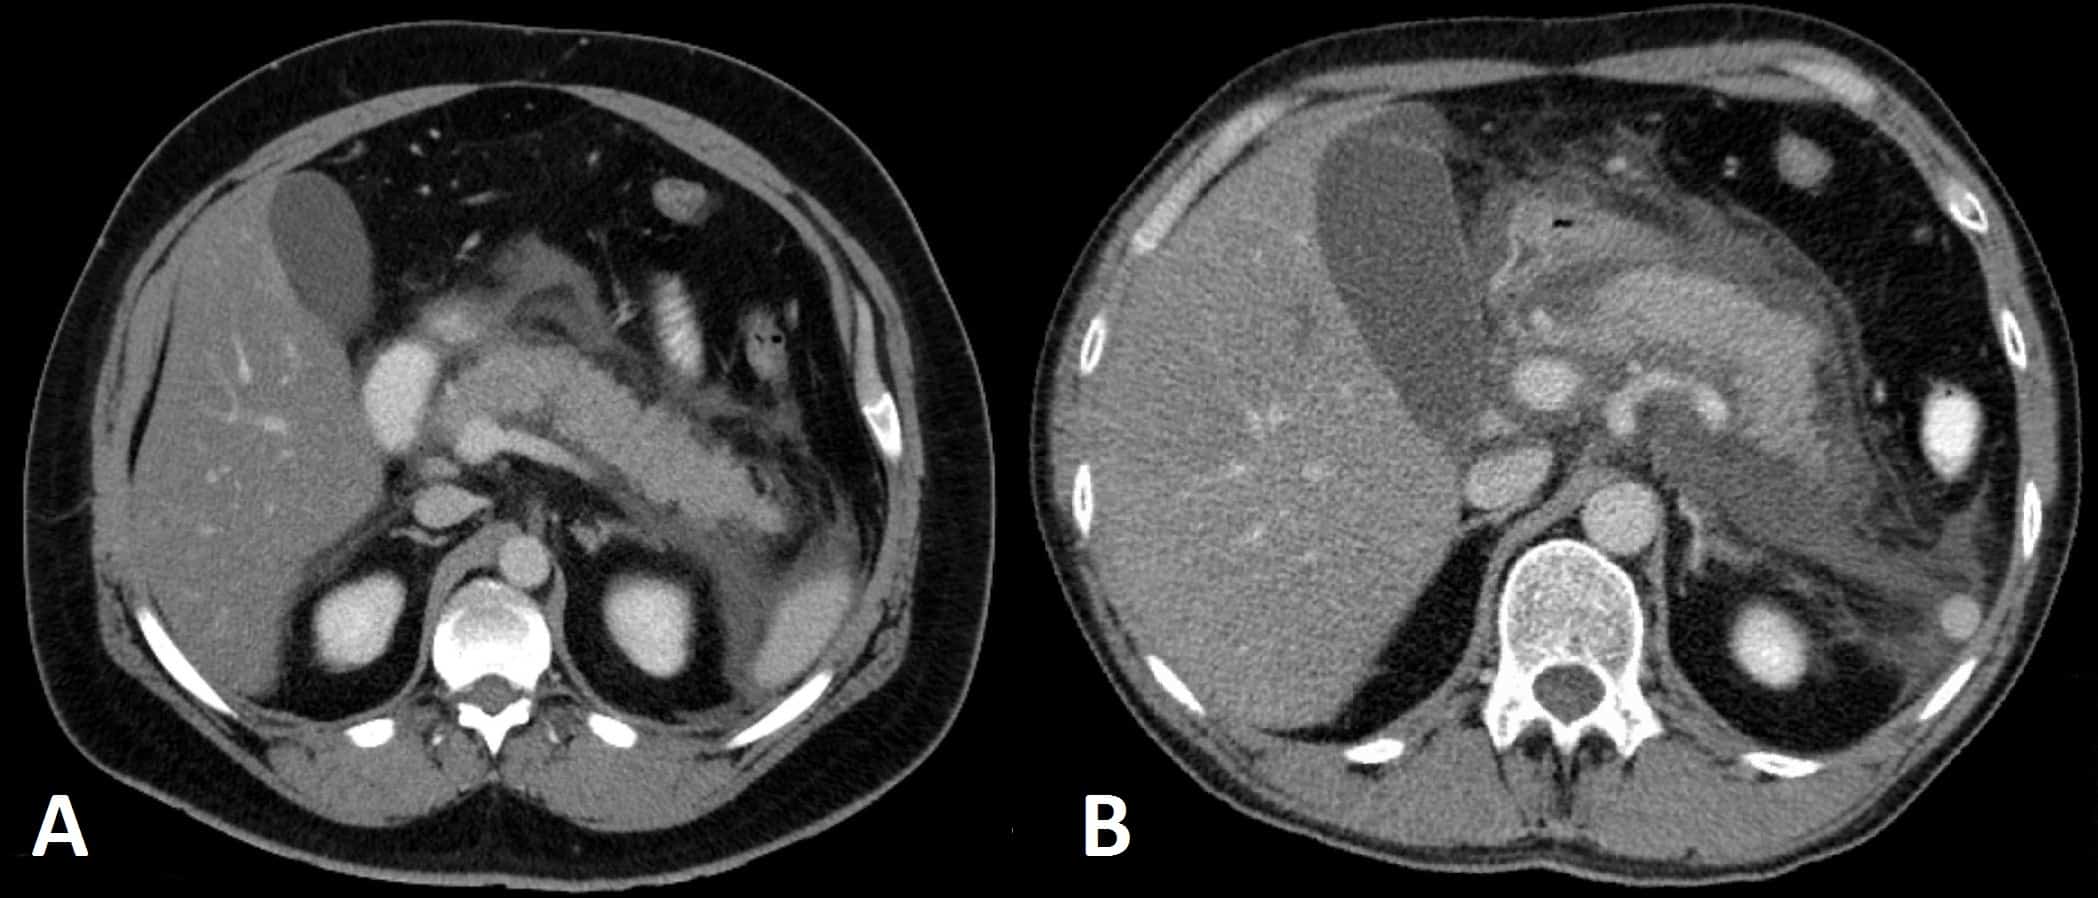

A contrast-enhanced CT scan (Fig. 3) may be required if the initial assessment and investigations prove inconclusive. If performed after 48hrs from initial presentation, it will often show areas of pancreatic oedema and swelling, or any non-enhancing areas suggestive of pancreatic necrosis.

Current UK guidelines state that any CT scan used to assess for severity of disease should only be performed 6-10 days after admission in patients with features of persistent inflammatory response or organ failure*.

*Prior to this time frame, CT-based severity scoring systems have been shown to be equivocal to clinical scoring systems in predicting severity, whilst increasing length of hospital stay with no improvement in clinical outcome